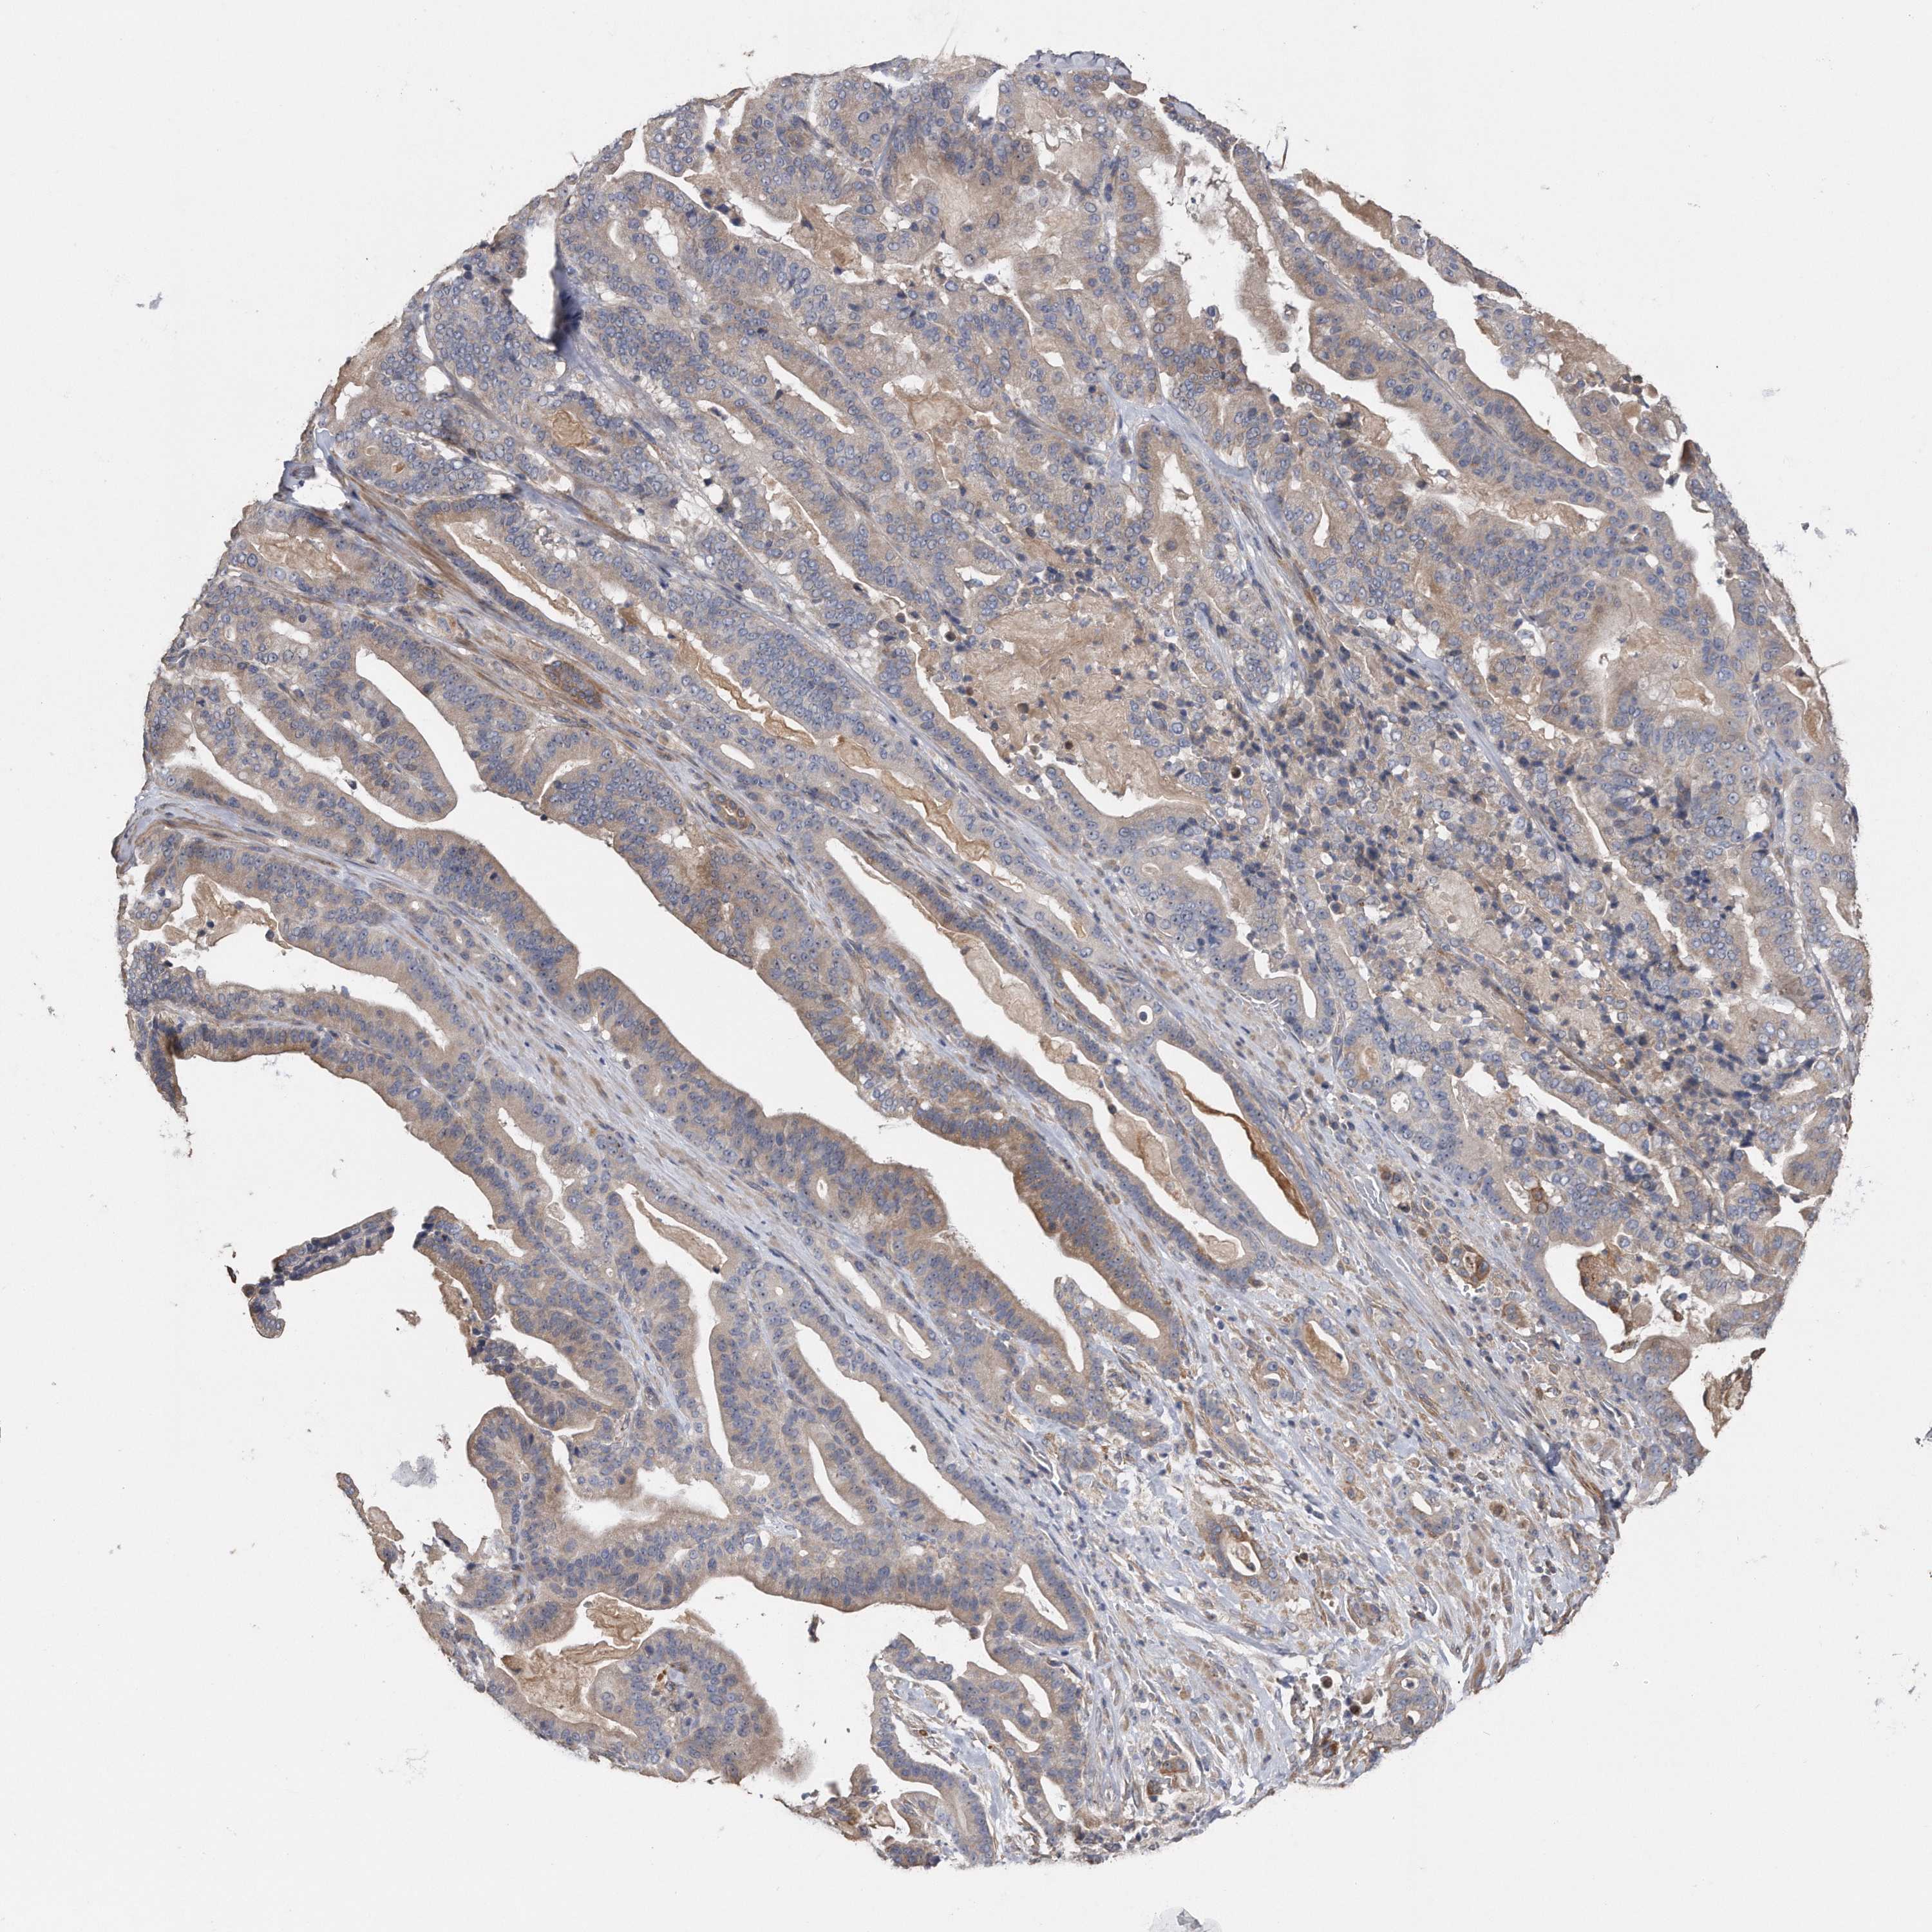

PANCREATIC CANCER - Protein expressioni

A mouse-over function shows sample information and annotation data. Click on an image to view it in a full screen mode. Samples can be filtered based on level of antibody staining by selecting one or several of the following categories: high, medium, low and not detected. The assay and annotation is described here.

Note that samples used for immunohistochemistry by the Human Protein Atlas do not correspond to samples in the TCGA dataset.

Antibody stainingi

Antibody staining in the annotated cell types in the current human tissue is reported as not detected, low, medium, or high, based on conventional immunohistochemistry profiling in selected tissues. This score is based on the combination of the staining intensity and fraction of stained cells.

Each image is clickable and will lead to virtual microscopy that enables deeper exploration of all samples and also displays staining intensity scores, fraction scores and subcellular localization as well as patient and tissue information for each sample.

Antibody HPA029452

Staining

High

Medium

Low

Not detected

Intensity

Strong

Moderate

Weak

Negative

Quantity

>75%

75%-25%

<25%

None

Location

Nuclear

Cytoplasmic/membranous

Cytoplasmic/membranous,nuclear

Adenocarcinoma, NOS